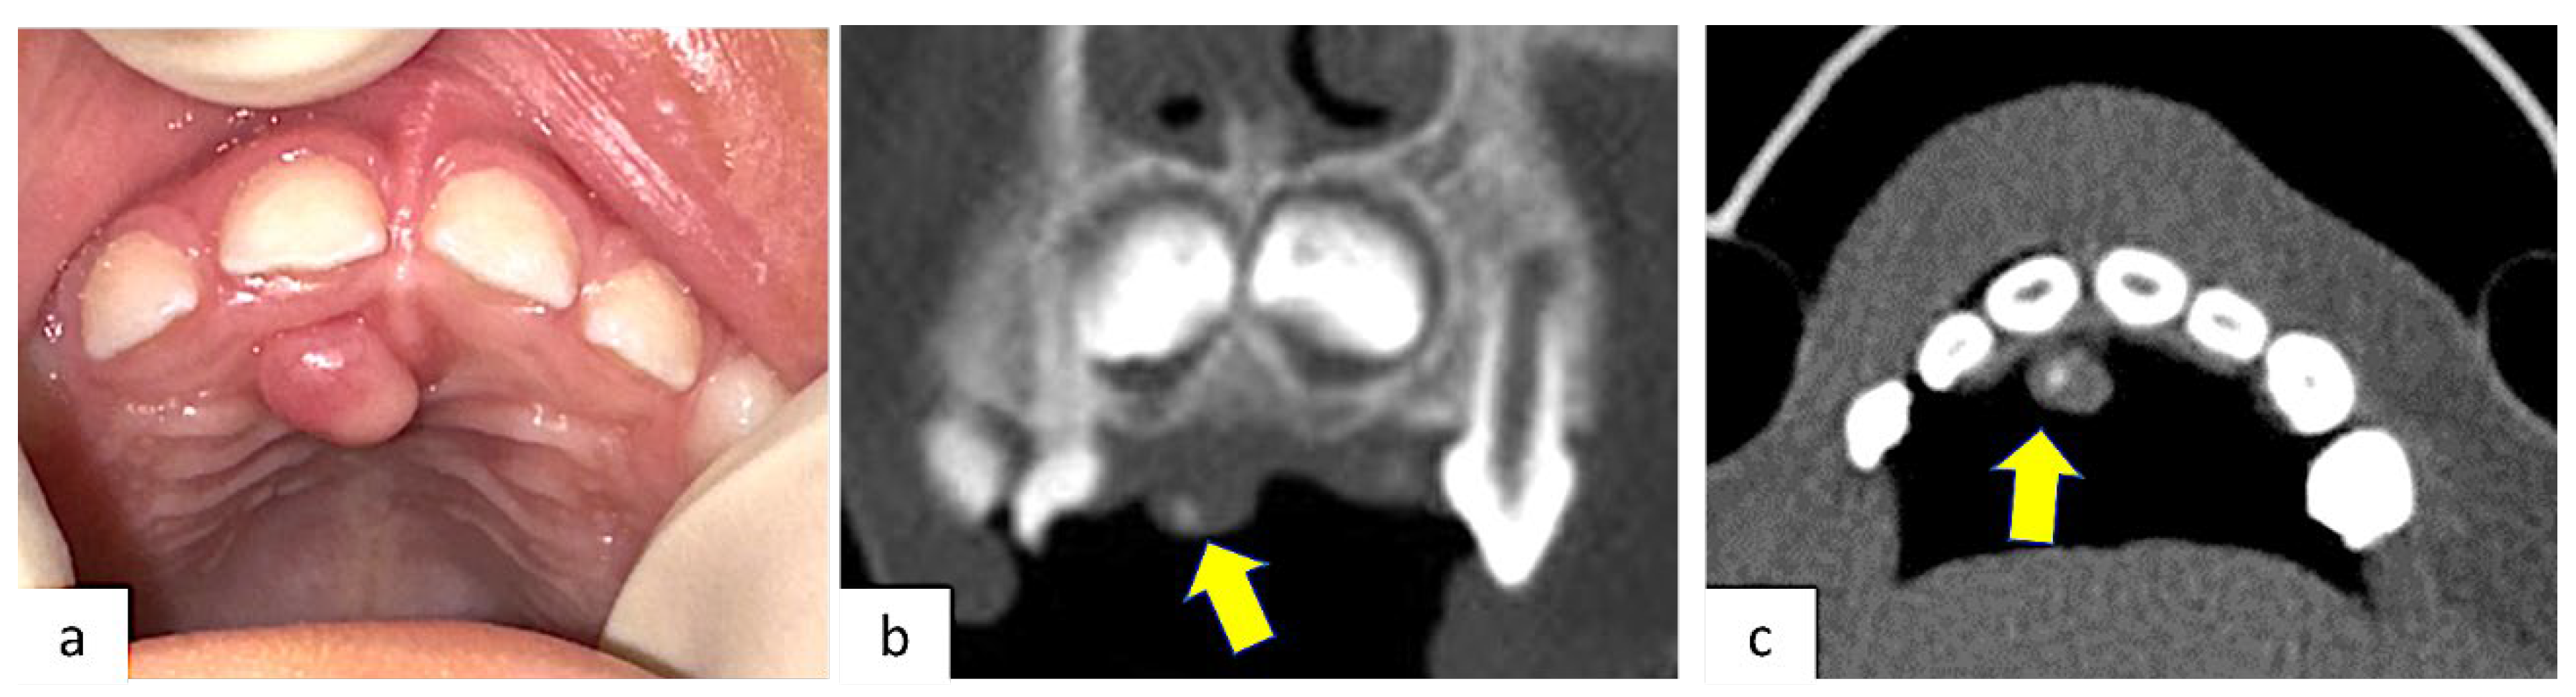

2015 | 1 | 11 | F | Anterior maxilla Right canine region |

4 × 3 cm | sessile exophytic lesion without changes in color, indurations, or ulceration. | OPT CT |

General anesthesia | POF | No |